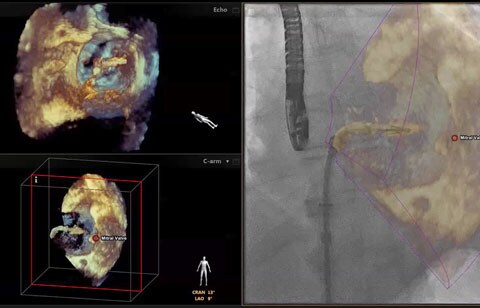

بعد تشخيص مريض بارتجاع الصمام الميترالي، ما هي خيارات العلاج المتوفرة له؟ إذا لم يكن مرشحًا للخضوع لعملية القلب المفتوح، يمكنك التفكير في معالجته عبر إصلاح الصمام الميترالي باستخدام القسطرة (TMVR). وفي يومنا الحالي، تؤمن حلول التصوير المبتكرة والأجهزة المتوفرة حديثًا خيارات جديدة لبعض المرضى.